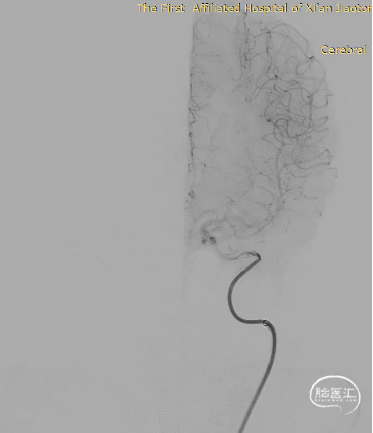

经Fastrack微导管输送FD到位

缓慢回撤Fastrack微导管,FD头端在颈内动脉末端V形打开,确认FD远端锚定点位于A1分叉近端

继续缓慢回拉释放支架

虹吸弯处适当推拉,使支架贴壁良好

支架完全完全打开,完全覆盖全部动脉瘤

撤出FD推送导丝

“J”型导丝成袢进行支架内按摩,使支架充分贴壁

造影显示动脉瘤内造影剂滞留

Vaso I.A. CT检查,支架完全打开,位置及贴壁良好,动脉瘤内部分造影剂滞留